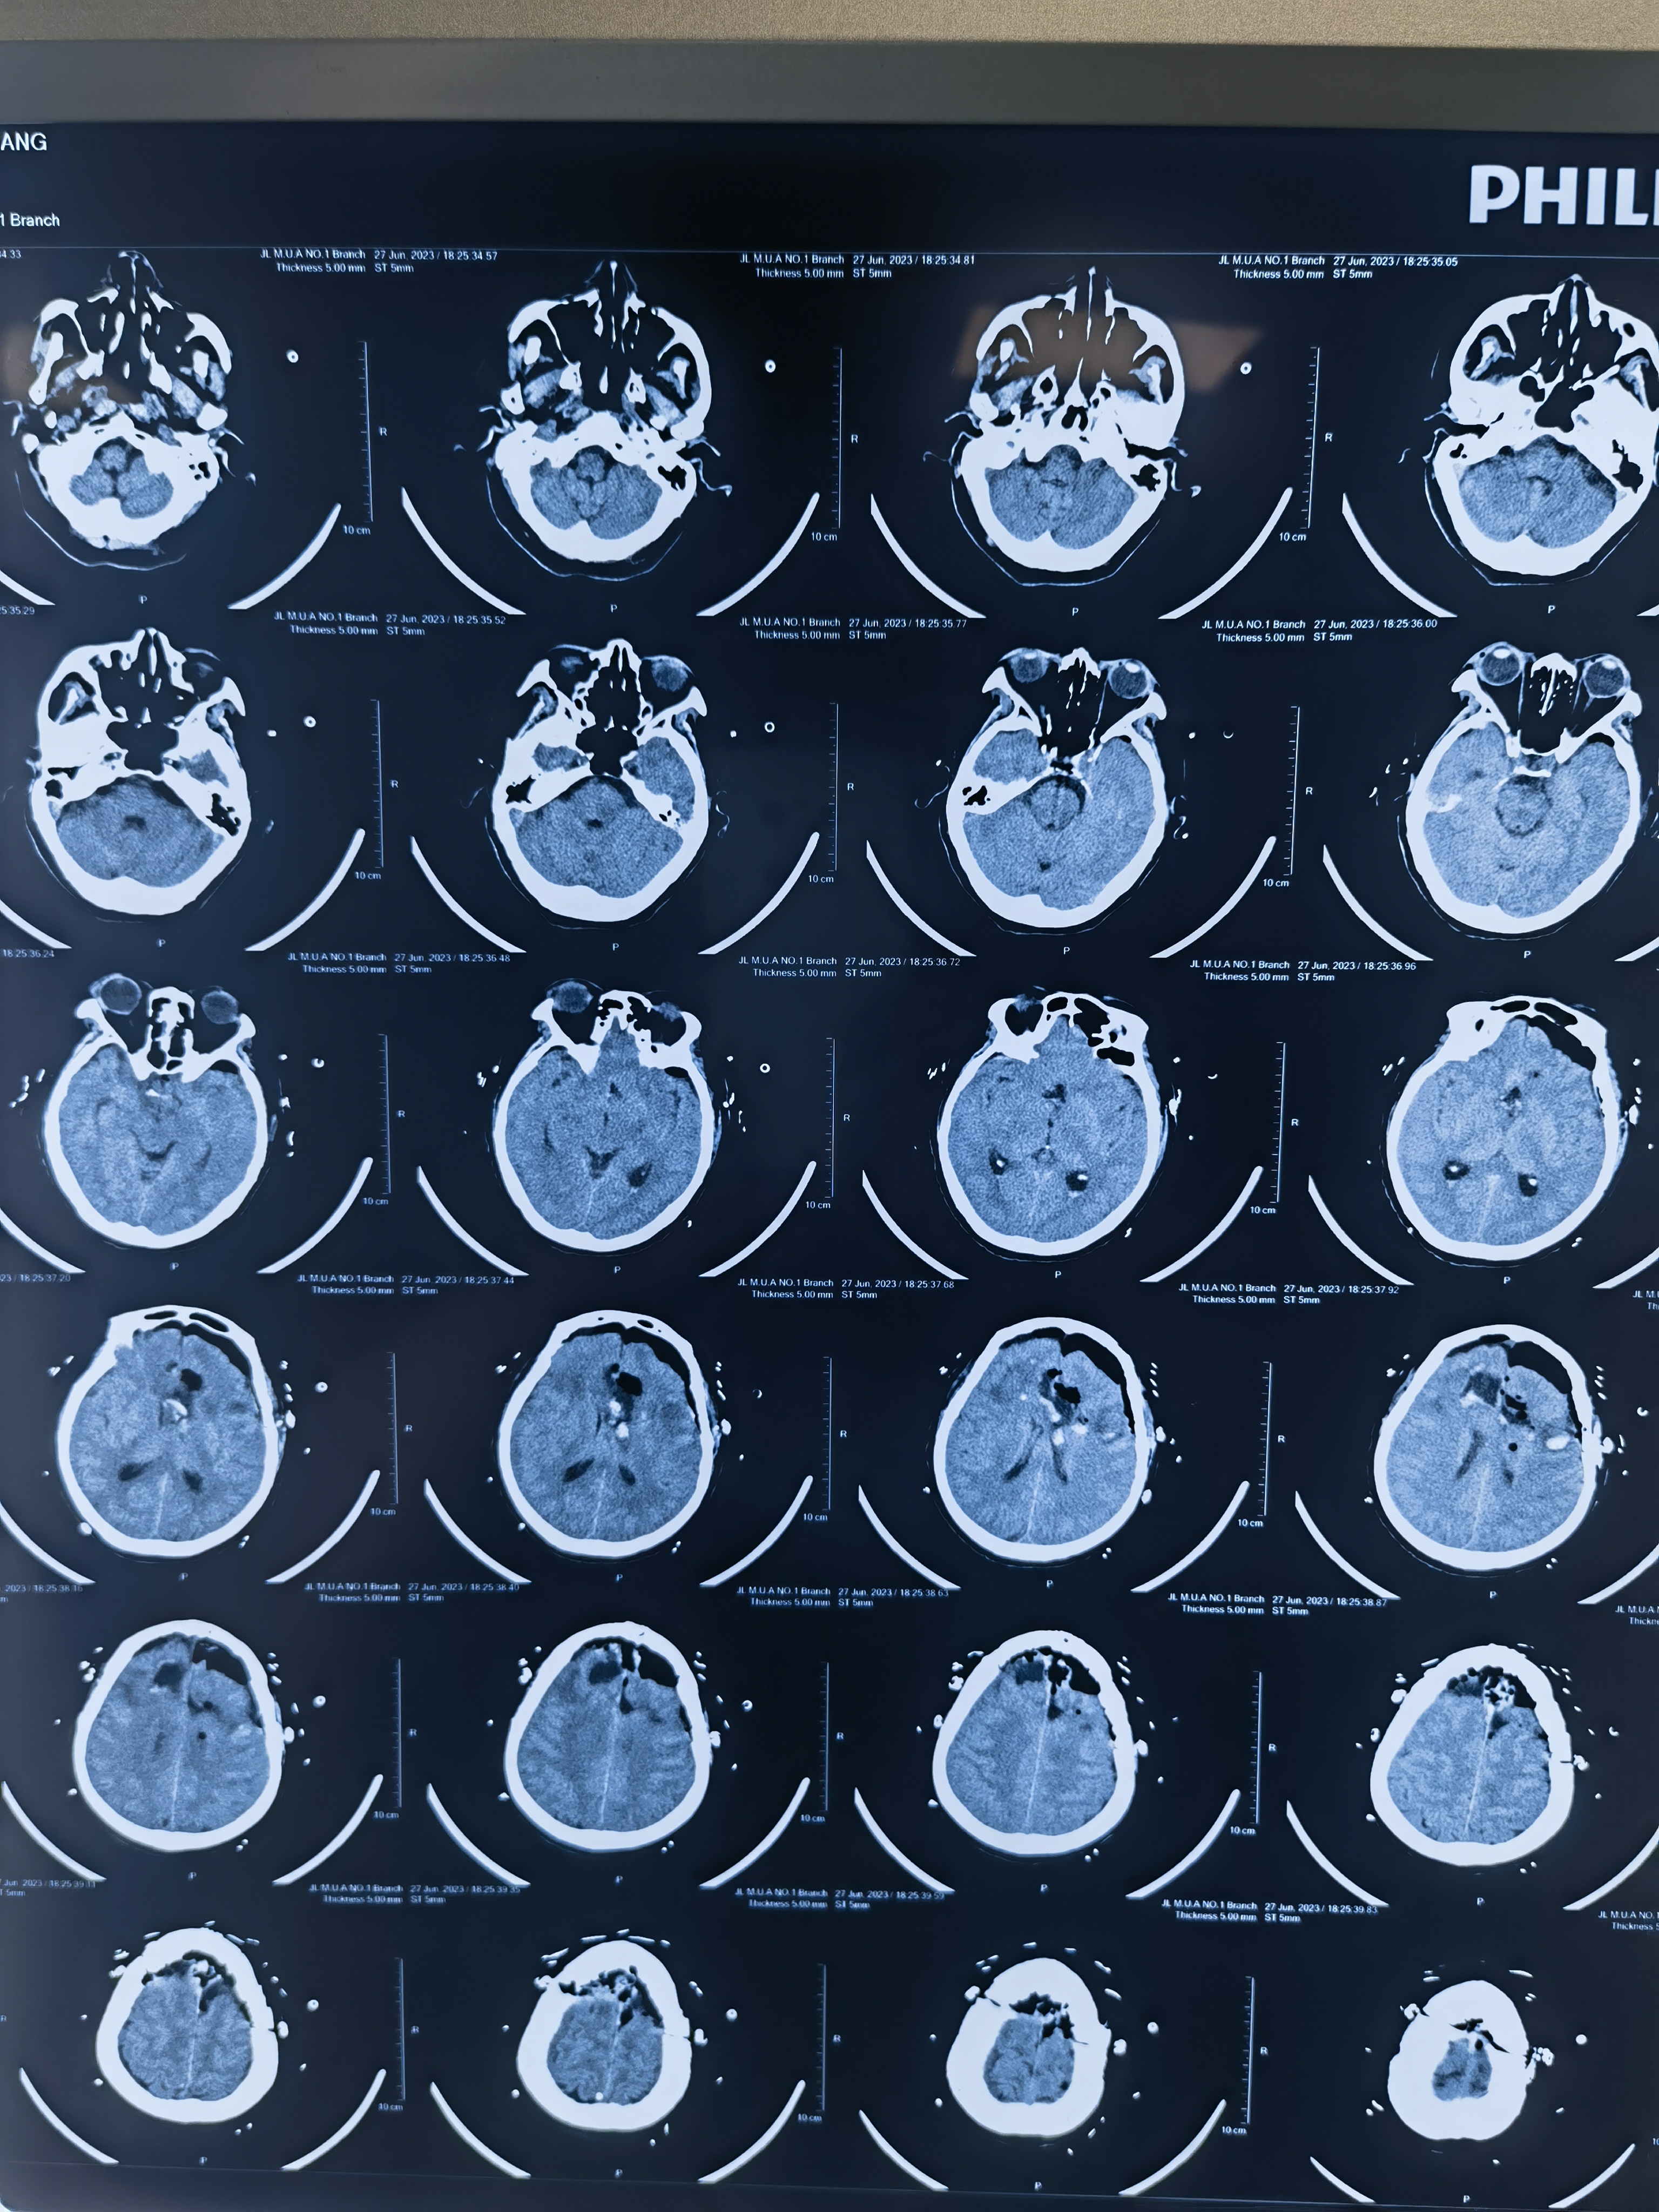

术后CT及增强核磁:

瘤腔偏右侧有部分肿瘤残余,与术中肿瘤失去血运,边界欠清有关。术后放疗时可重点关注此部位。

术后患者表情缄默,反应慢,考虑与胼胝体膝部下丘脑损伤有关。患者有不完全运动性失语,与左侧运动性语言中枢受损有关,后期会不同程度恢复。

胶质母细胞瘤当完全失去血运时,有时与周围脑组织界限难以分辨,主要质地会稍韧,需要术者通过手感来分辨。非功能区需要扩大切除才能达到彻底切除的效果。但该患左侧损伤较重,为避免出现四肢瘫,右侧切除相对保守。

累及胼胝体膝部肿瘤是能够达到影像学意义的全切的,术后病人淡漠,反应迟钝症状往往较轻。此例患者考虑下丘脑损伤所致意识水平较差。

高级别胶质瘤术后48小时增强核磁复查非常重要,能帮助我们早期发现是否有肿瘤残余和评估预后。